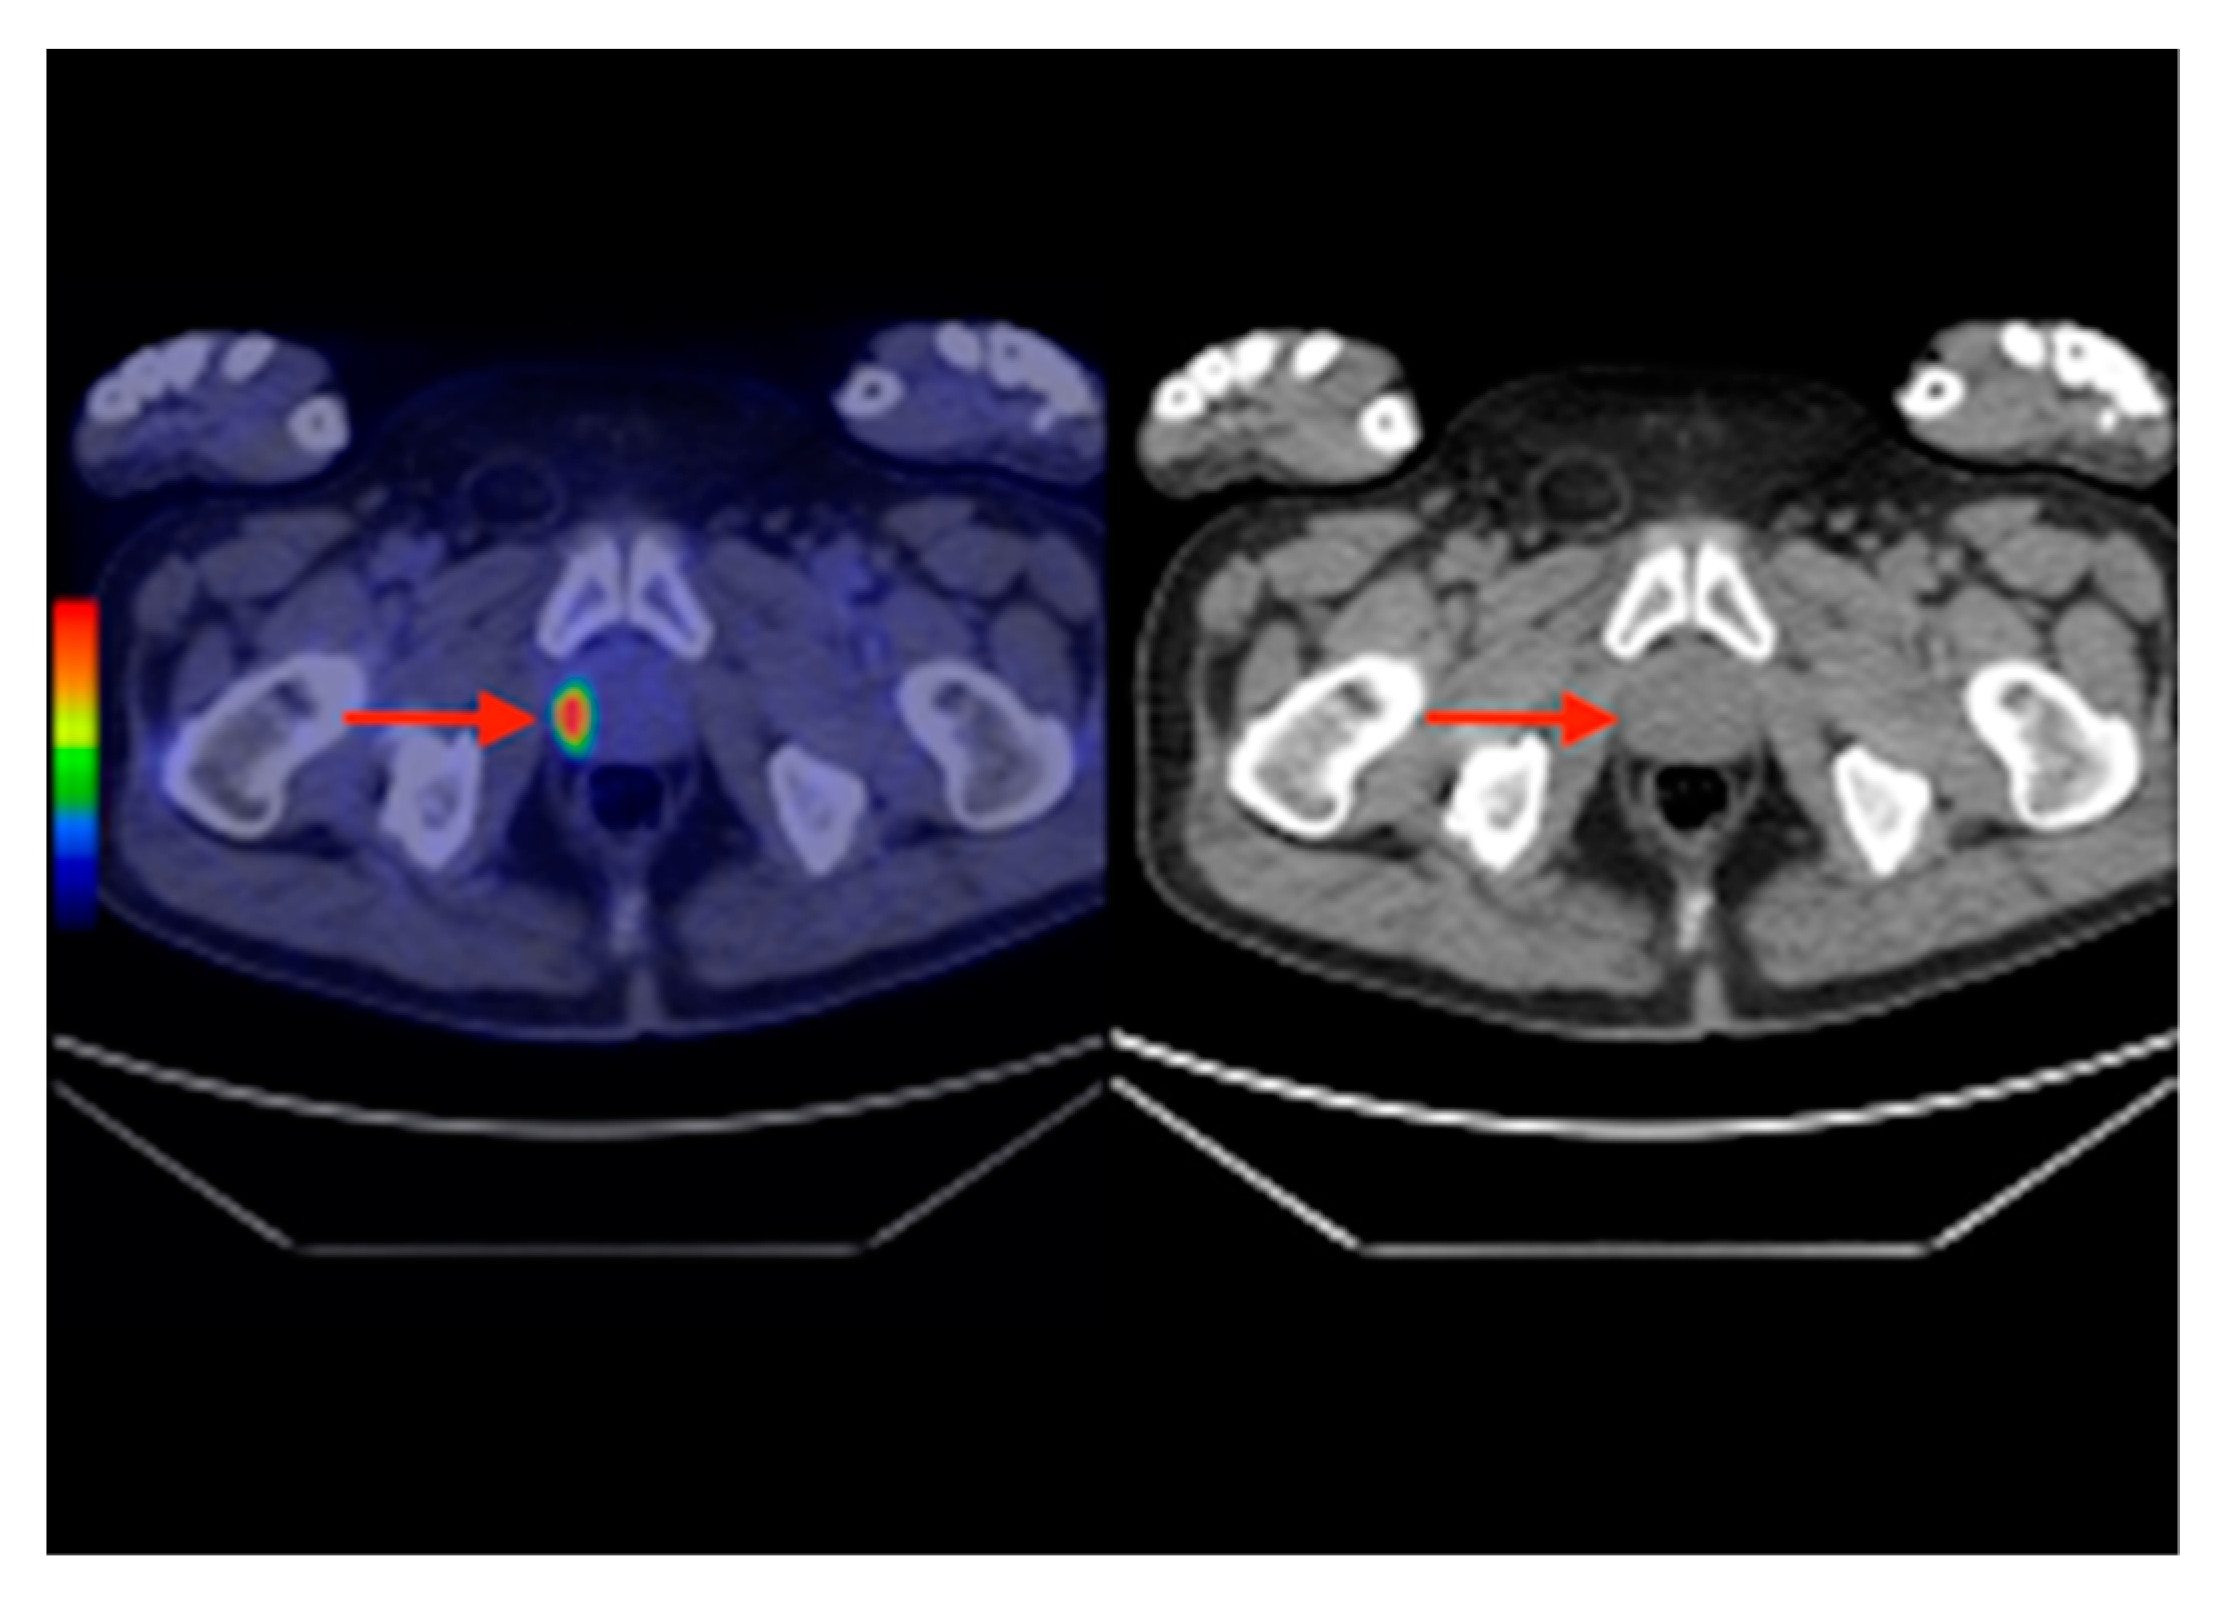

In 2007, an F18-FDG PET-CT scan was performed, which revealed a 30/28 mm focal increase of uptake in the sigmoid colon and a lesion of 21 mm in the VIIth liver segment, consisting of a colon malignant tumor with liver metastases (Figure 6). The patient was submitted for hemicolectomy and liver metastases resection, followed by chemotherapy. In 2013, during the routine examination, we found a focal uptake in the right prostatic lobe. After the prostatectomy, the histopathological result showed a prostate adenocarcinoma, occurring in a patient with already known thyroid and colon carcinomas (Figure 7).

Figure 7. Axial section F18-FDG PET-CT (left) and CT (right) revealing an increased uptake in the right prostate lobe (red arrows) suggesting a primary prostate carcinoma, confirmed in histology.